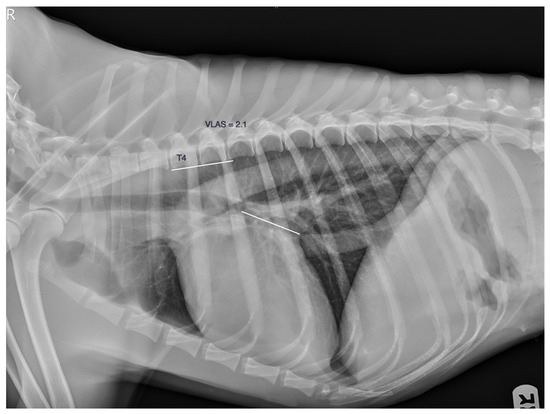

- Malcolm, E.L.; Visser, L.C.; Phillips, K.L.; Johnson, L.R. Diagnostic value of vertebral left atrial size as determined from thoracic radiographs for assessment of left atrial size in dogs with myxomatous mitral valve disease. J. Am. Vet. Med. Assoc. 2018, 253, 1038–1045. [Google Scholar] [CrossRef]